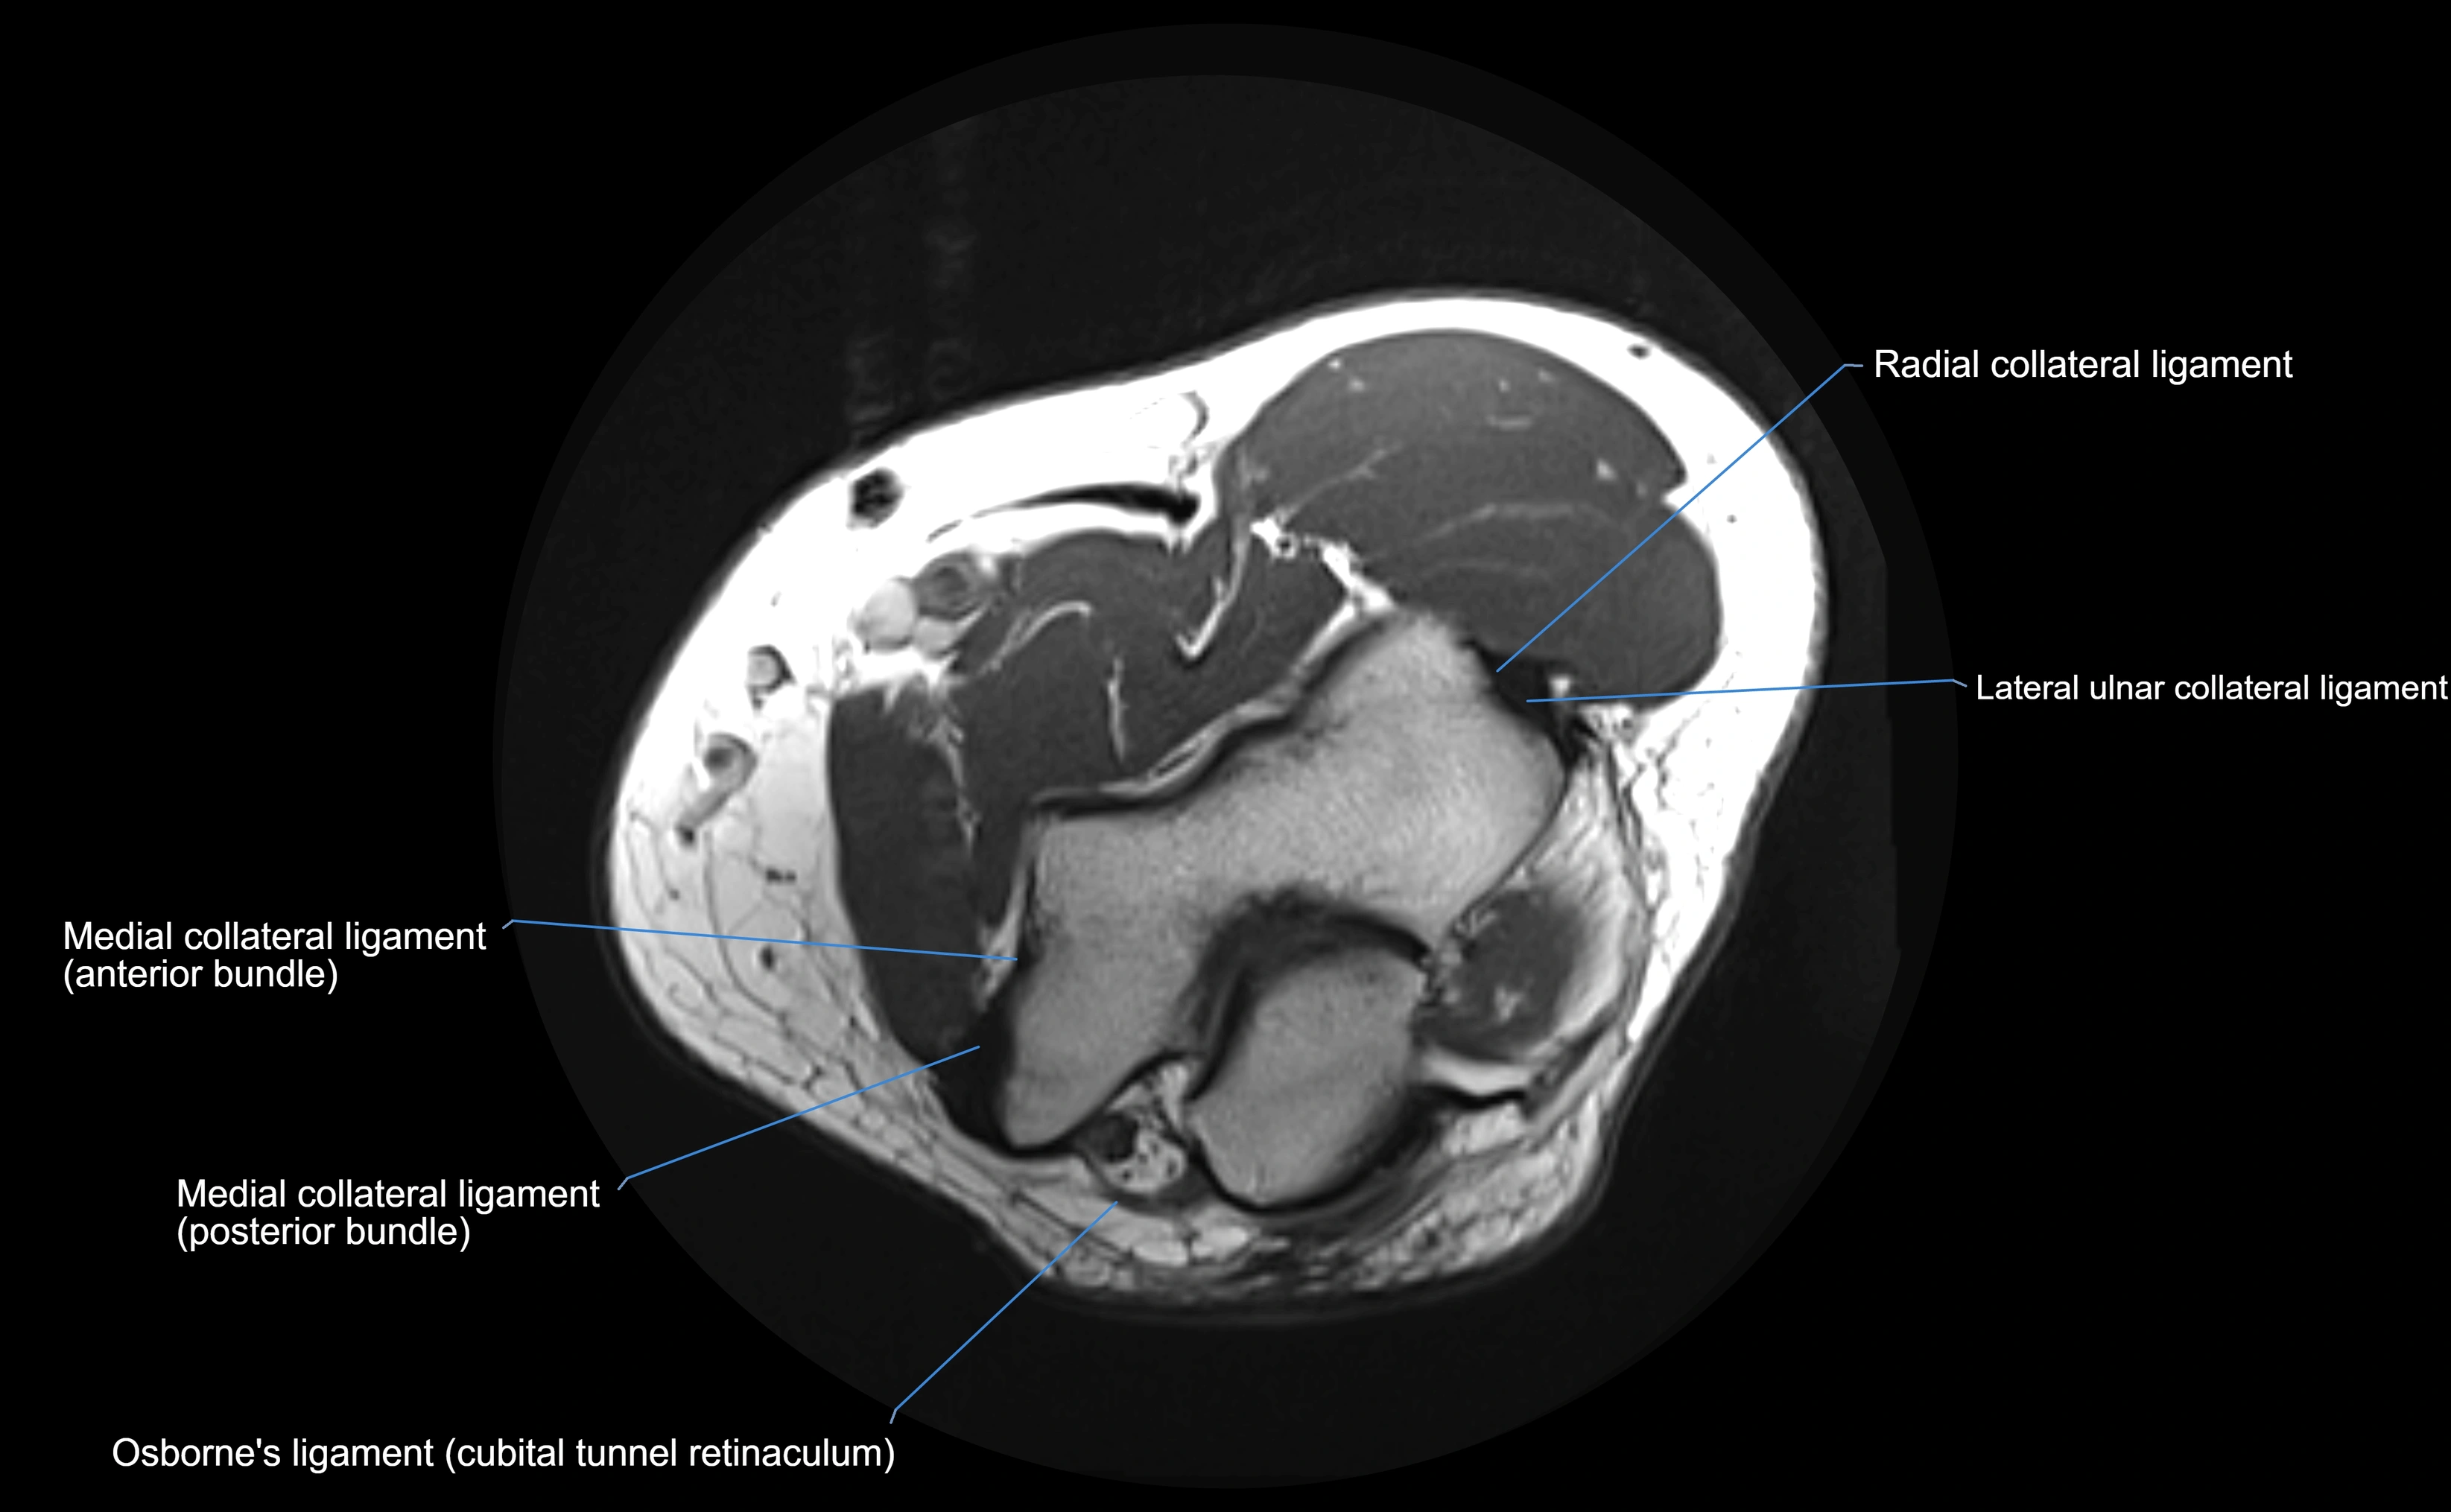

MRI Appearance

T1-weighted images:

• Ligament: low signal intensity (dark), appearing as a continuous band around the radial head.

• Adjacent fat and marrow: bright, creating contrast with the ligament.

• Thickening or disruption indicates injury or fibrosis.

• Joint capsule and synovium seen as thin low-signal lines contiguous with ligament margins.

T2-weighted images:

• Ligament: low signal (dark) with clear delineation from joint fluid.

• Fluid or edema: bright hyperintense, separating or surrounding the ligament in partial tears.

• Complete tear: discontinuity or non-visualization of ligament fibers, often with joint effusion.

Proton Density Fat-Saturated (PD FS):

• Normal: dark, well-defined band outlining the radial head.

• Partial tear: irregular or bright hyperintense signal within or adjacent to ligament fibers.

• Joint effusion and reactive synovitis appear bright and are well visualized.

MRI images

image